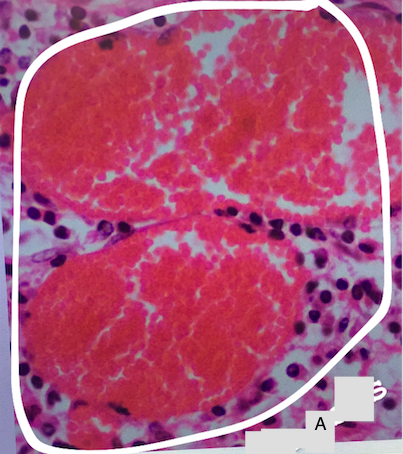

Label this photo